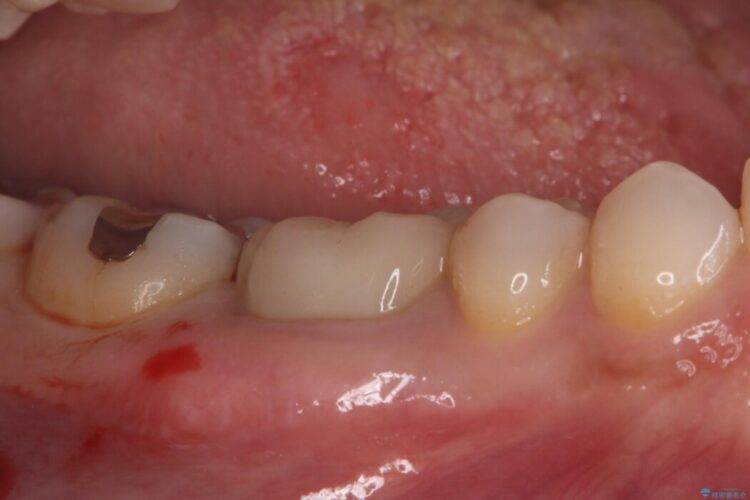

診査の結果、古い銀歯の隙間から新しい虫歯が広がっていました。ここは噛む力が強くかかる場所のため、このまま詰め物で治すと、部分的な詰め物では残存している自分の歯に負担が集中し、将来的に歯が割れてしまう「歯冠破折」のリスクが高い状態でした。

虫歯を丁寧に除去し、審美性・耐久性に優れたセラミッククラウンにやり替える治療計画を立案しました。